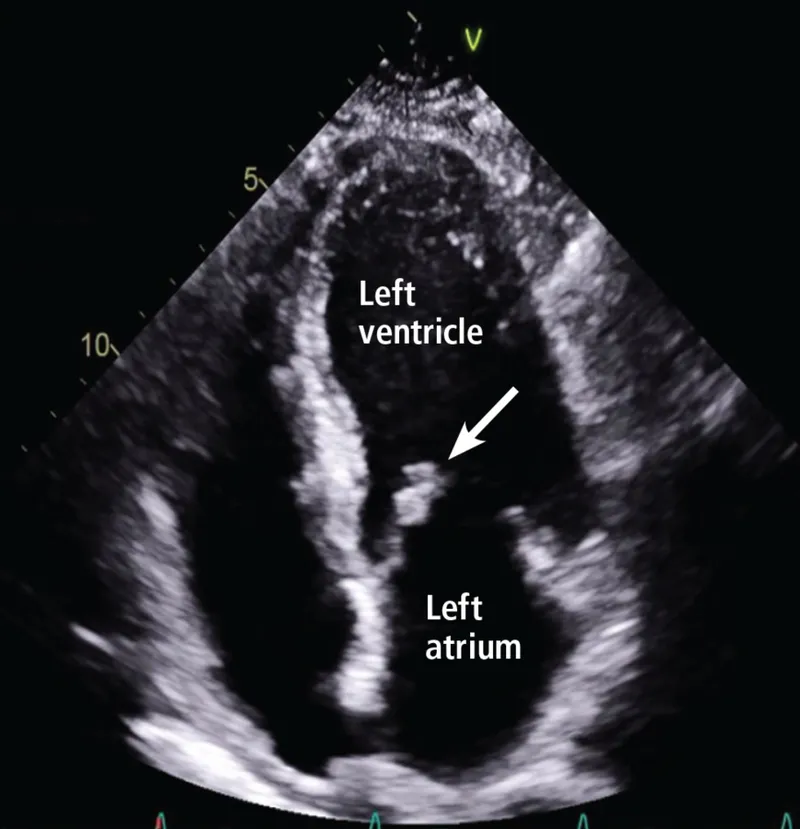

Echocardiography - Ultrasound Heart Peeks

Uses ultrasound waves for real-time imaging of heart anatomy, function, and hemodynamics.

- 2D/M-mode: Structure, dimensions, LVEF (Normal: >55%).

- Doppler (Color, PW, CW): Blood flow, valvular lesions, shunts. $P = 4v^2$ (Modified Bernoulli for pressure gradients).

- TEE (Transesophageal Echo): Superior for posterior structures (LA/LAA, MV, aorta), endocarditis, aortic dissection.

⭐ TEE is superior to TTE for visualizing small vegetations (<5mm) in infective endocarditis and for detecting left atrial appendage (LAA) thrombus prior to cardioversion for atrial fibrillation.